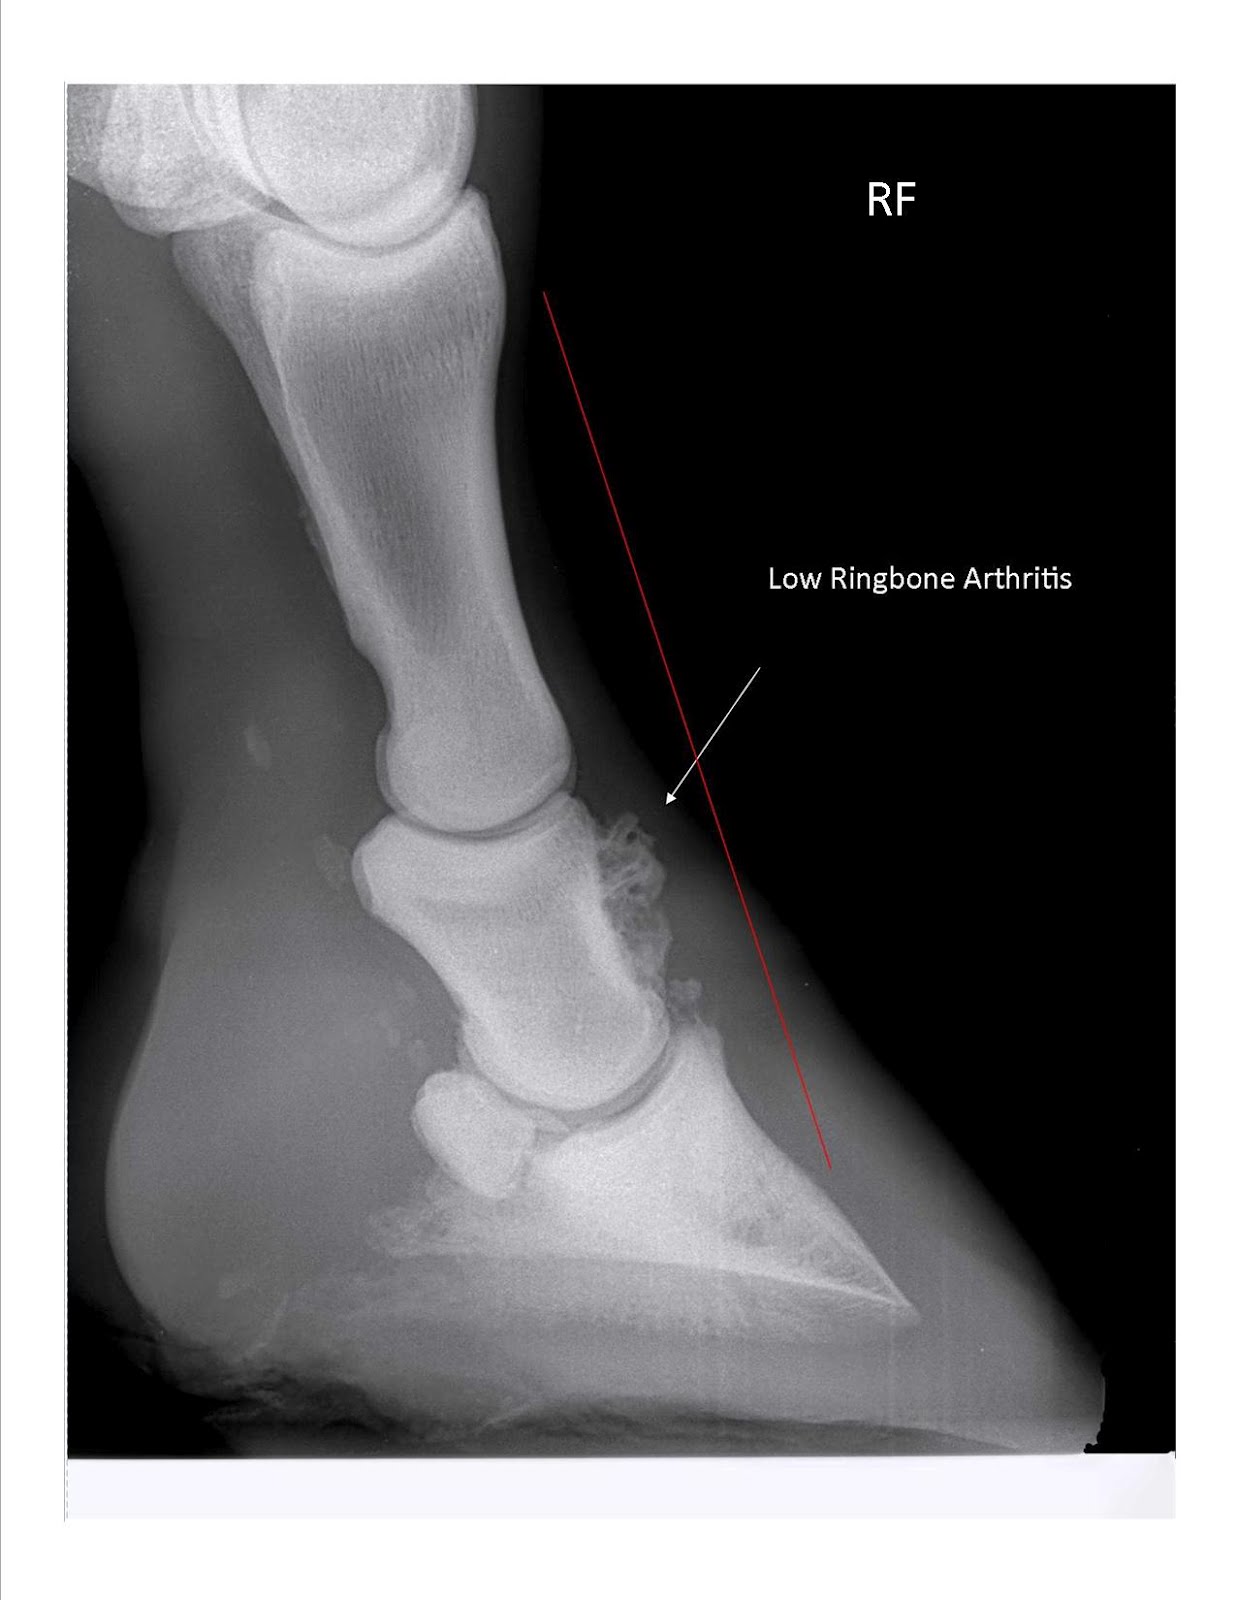

Case Study Horse with Low Ringbone Butler Professional Farrier Schools Ring Bone Xray ringbone is a disease that does not discriminate; The joint surfaces are usually very. High ringbone affects the pastern, and low ringbone affects the coffin. “most of the time, diagnostics will consist of x rays. Then, specific measures aimed at. The horse’s leg is positioned and immobilized so images of the distal limb can be taken. But if. Ring Bone Xray.

Ring bone in horses Etiology, Clinical Sign, Diagnosis & Treatment Ring Bone Xray High ringbone affects the pastern, and low ringbone affects the coffin. ringbone is a disease that does not discriminate; An arthritic, degenerative disease of the pastern and coffin joints, ringbone comes in two types. The joint surfaces are usually very. Horses of all breeds, ages, and functions can be at risk. Then, specific measures aimed at. ringbone is. Ring Bone Xray.

Ringbone 101 US Equestrian Ring Bone Xray “most of the time, diagnostics will consist of x rays. But if we don’t get an answer with x rays, we can do mri, bone scans (aka nuclear scintigraphy), or ultrasound. Horses of all breeds, ages, and functions can be at risk. ringbone is a disease that does not discriminate; An arthritic, degenerative disease of the pastern and. Ring Bone Xray.